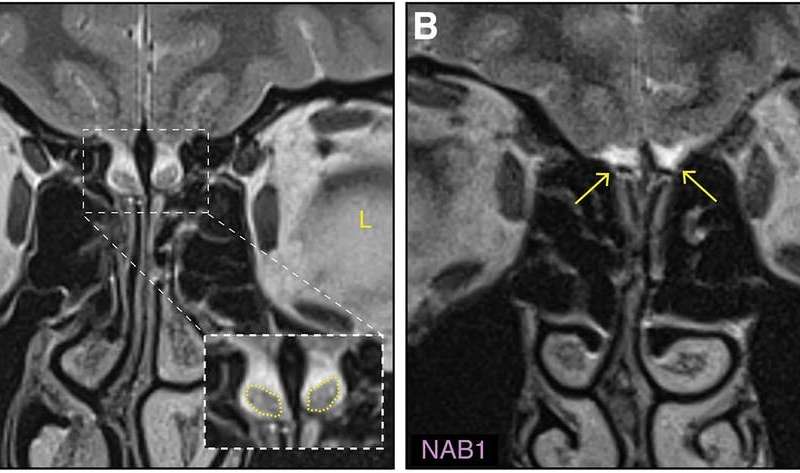

Исследователи обнаружили у девушки удивительную аномалию — отсутствие обонятельных луковиц при сохранном обонянии. Попробуем разобраться, почему это возможно и как мозг справляется с необходимостью «заменять» проблемные участки.